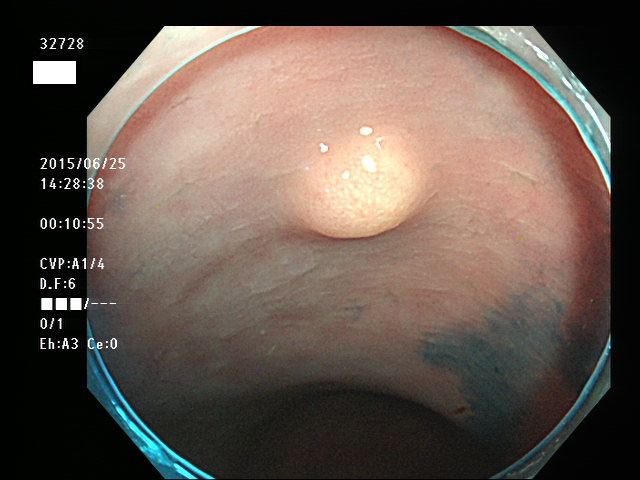

上記100名より抽出した平坦・陥凹型腺腫(=癌化の危険が高いが見落としやすい病変)の内視鏡写真

32723 32725 32726 32728 32734 32735 32737 32738 32739 32742 32743 32745